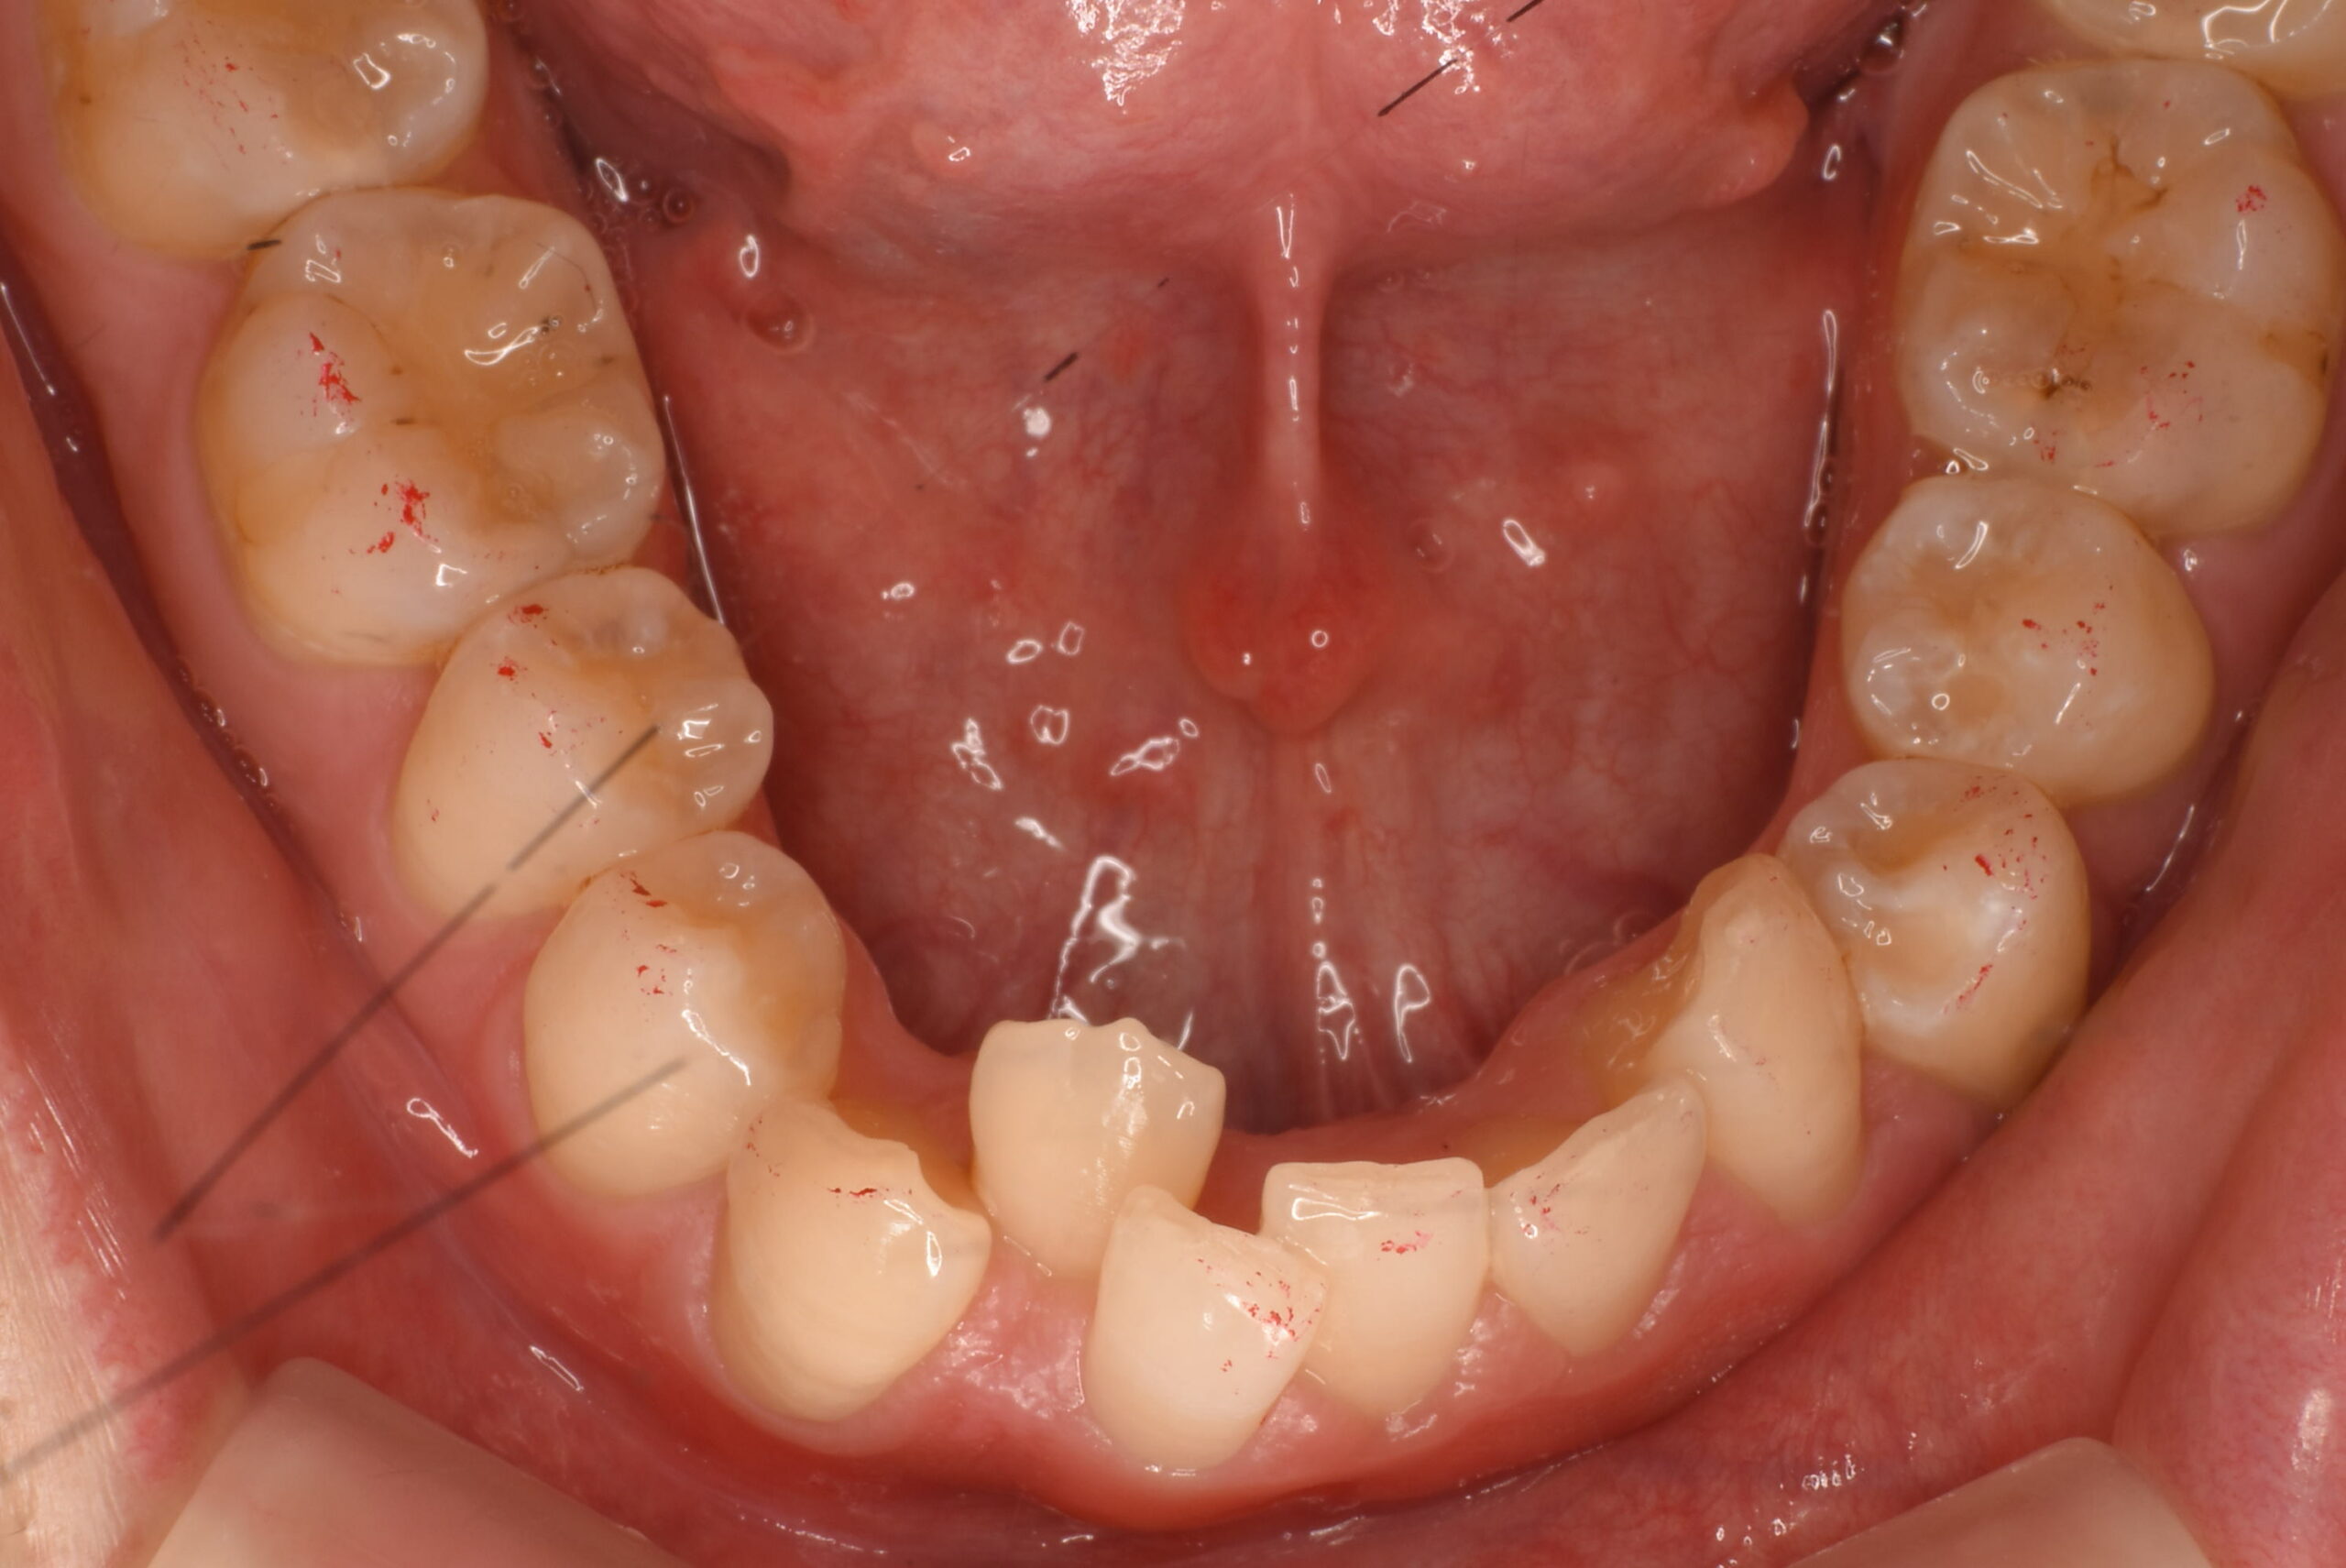

治療前_下顎咬合面

-